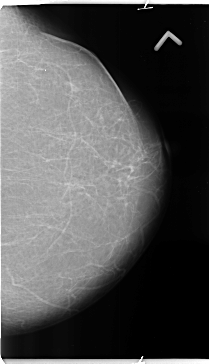

B_3135_1.LEFT_MLO

LEFT_MLO LINES 4752 PIXELS_PER_LINE 2872 BITS_PER_PIXEL 12 RESOLUTION 50 NON_OVERLAY